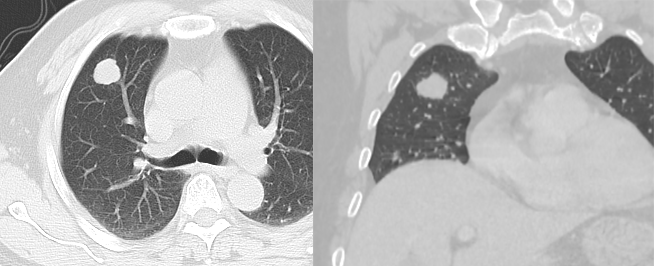

文献报道空洞型肺转移主要来自鳞癌和腺癌,鳞癌占 1/2-2/3,主要来自男性头颈部与女性生殖器肿瘤,其余为腺癌,主要来自结肠与乳腺癌。单亦有研究认为空洞性转移主要来自腺癌。其产生机制可能与鳞癌中心角化物排空、腺癌黏液样退变后黏液排空、肿瘤血供不足引起坏死、肿瘤继发脓肿、化疗、阻塞性肺气肿等有关。空洞性肺转移瘤变化快,短期内可见肿瘤增大、增多。CT 上空洞型转移结节外形上多保持了转移瘤的基本特点,即多发、圆形、边缘光整。洞壁多薄而均匀,内外壁光整,直径多 <1.0 cm,部分洞壁厚薄不均,厚壁空洞病变可随着病灶增大而出现分叶、毛刺及壁结节等恶性空洞特点,部分空洞型肺转移洞壁可菲薄(称空泡更合适)。

图片

乳腺癌空洞性肺转移。

54 岁男性,肾癌病史。左肺下叶厚壁空洞性转移(穿刺证实),左肺另见不伴空洞的实性小结节转移灶。